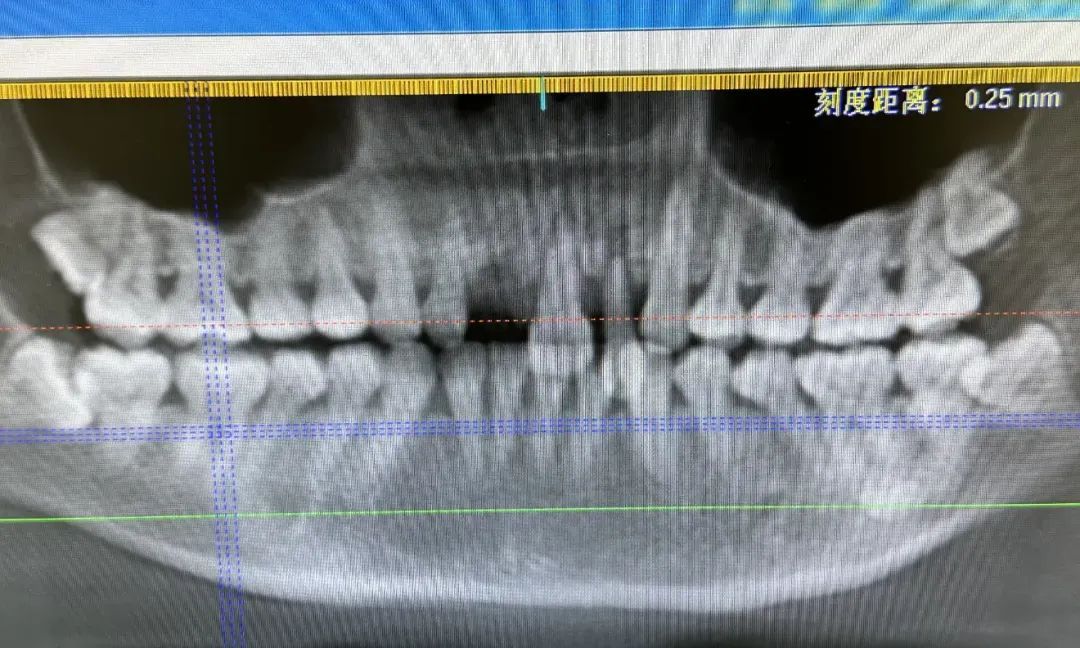

▲骑行者被摔后的牙齿情况

▲进行处理后的牙齿情况